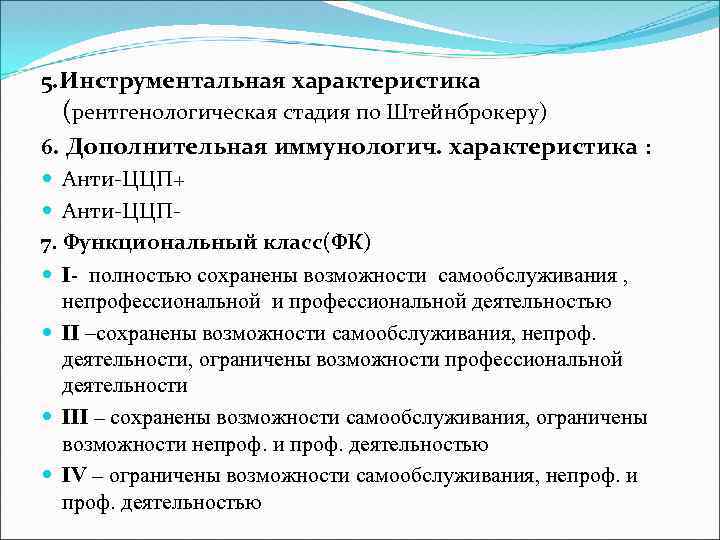

5. Инструментальная характеристика (рентгенологическая стадия по Штейнброкеру) 6. Дополнительная иммунологич. характеристика : Анти-ЦЦП+ Анти-ЦЦП 7. Функциональный класс(ФК) І- полностью сохранены возможности самообслуживания , непрофессиональной и профессиональной деятельностью ІІ –сохранены возможности самообслуживания, непроф. деятельности, ограничены возможности профессиональной деятельности ІІІ – сохранены возможности самообслуживания, ограничены возможности непроф. и проф. деятельностью ІV – ограничены возможности самообслуживания, непроф. и проф. деятельностью

5. Инструментальная характеристика (рентгенологическая стадия по Штейнброкеру) 6. Дополнительная иммунологич. характеристика : Анти-ЦЦП+ Анти-ЦЦП 7. Функциональный класс(ФК) І- полностью сохранены возможности самообслуживания , непрофессиональной и профессиональной деятельностью ІІ –сохранены возможности самообслуживания, непроф. деятельности, ограничены возможности профессиональной деятельности ІІІ – сохранены возможности самообслуживания, ограничены возможности непроф. и проф. деятельностью ІV – ограничены возможности самообслуживания, непроф. и проф. деятельностью